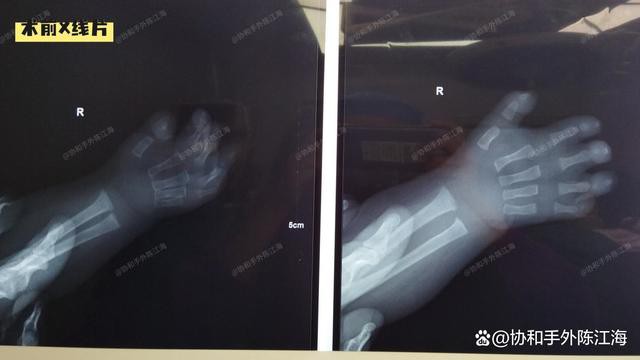

Rendgenski zraci prije operacije

Ova je beba klasični slučaj Poljskog sindroma. Prsti desne ruke relativno su kratki, a sva četiri prsta, osim palca, spojena su zajedno. Srećom, zglobovi su bili stabilni.Sa šest mjeseci, izvršili smo operaciju kako bismo odvojili sve spojene prste.

Prije operacije